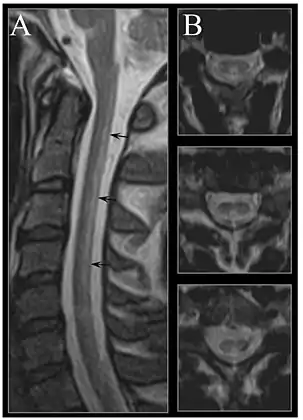

MRI of the brain may show periventricular white matter abnormalities. MRI of the spinal cord may show linear hyperintensity in the posterior portion of the cervical tract of the spinal cord, with selective involvement of the posterior columns.